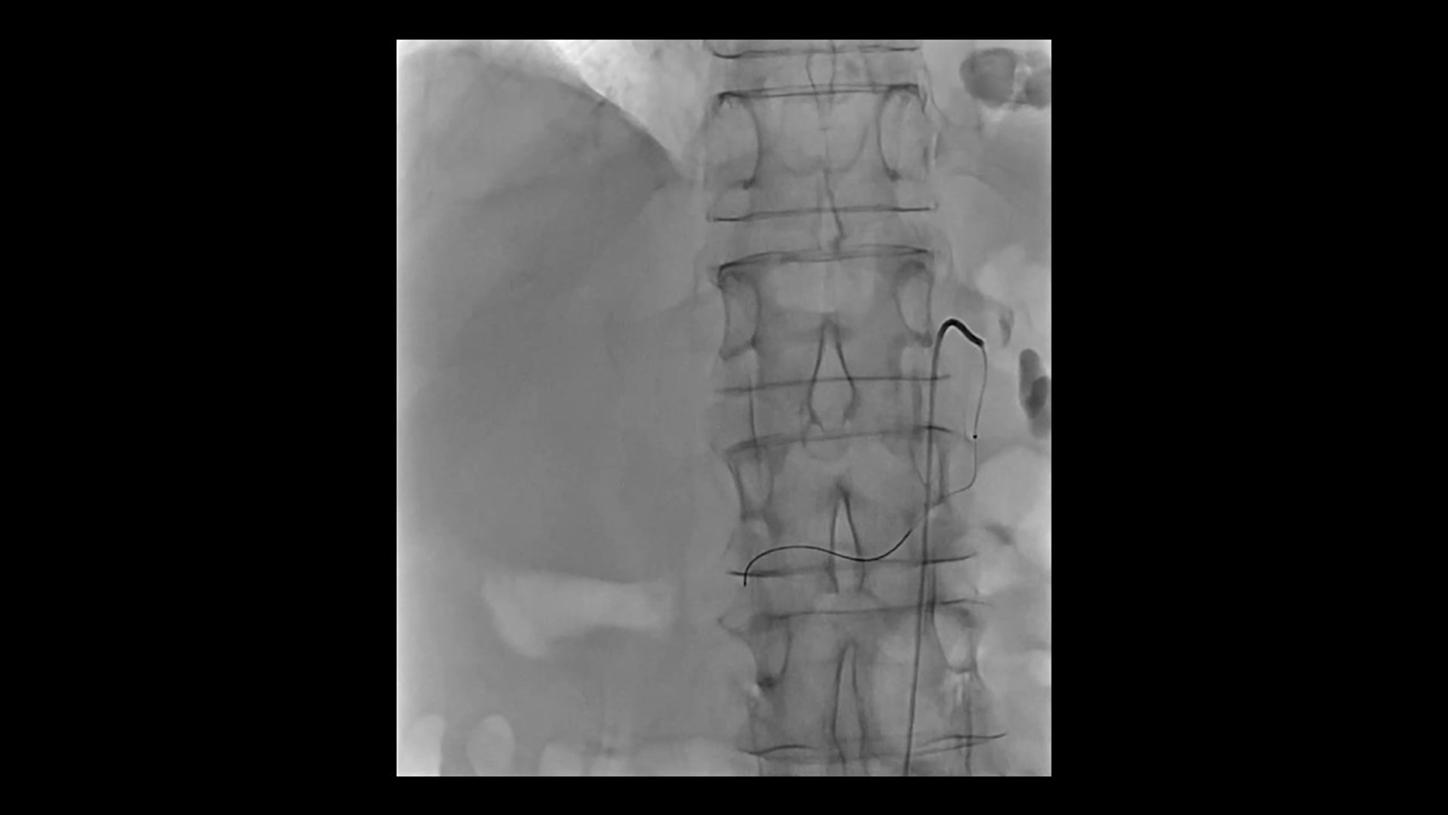

Future-focused IR imaging for a broad procedure mix

Discover how leading clinicians are transforming interventional radiology with Siemens Healthineers technologies. From ultra-fast 3D imaging to laser-guided needle procedures, the ARTIS icono ceiling powered by OPTIQ and syngo DynaCT are redefining what’s possible in IR. Explore real-world cases, expert insights, and the future of image-guided therapy.